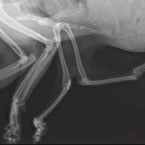

2015 – there is an update 2023: A stray cat, with six legs, abandoned on the streets of Edmonton, Canada has been rescued and plans are afoot to amputate the two extra legs which are non-functioning and attached to his chest. Pauly also has hip dysplasia (the ball and socket hip joint is defective). …